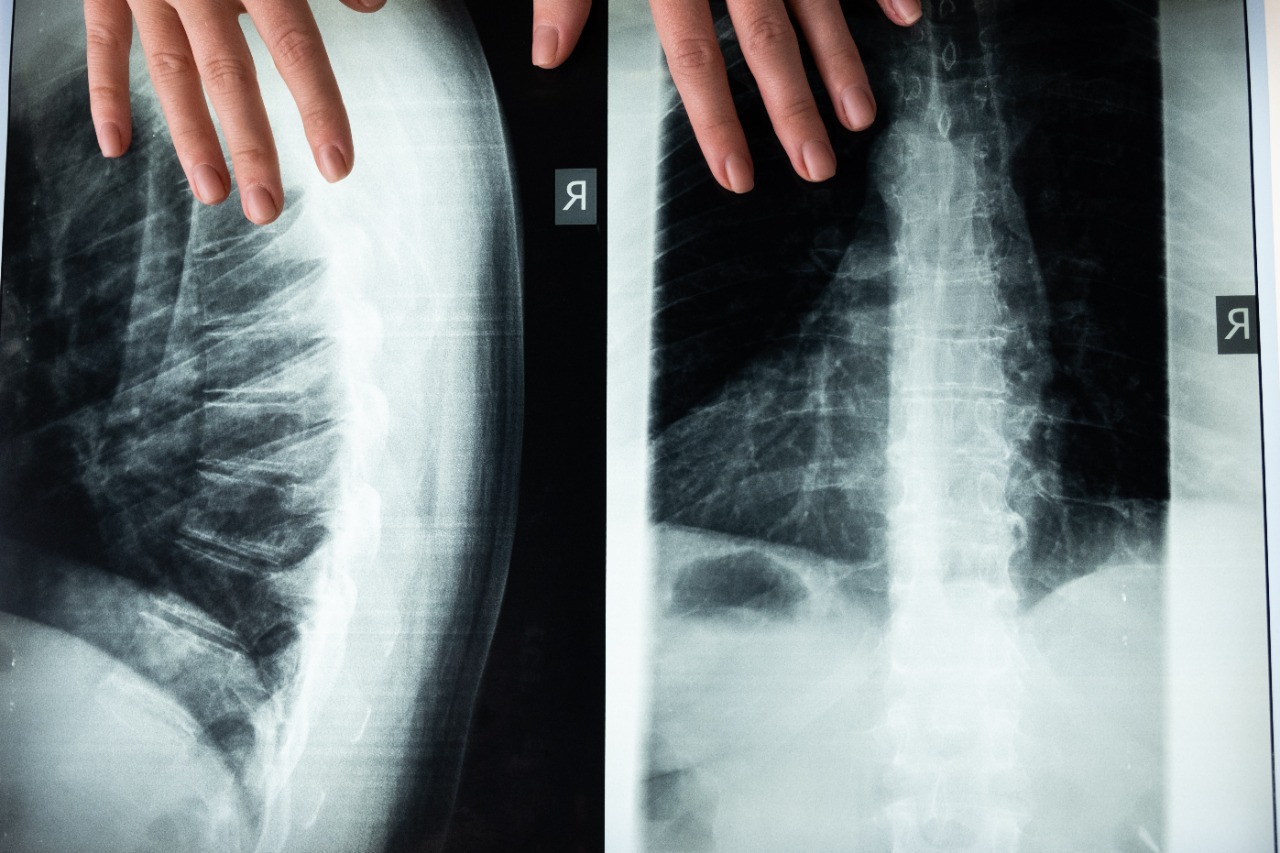

El examen puede complementarse con un ultrasonido dentro del primer mes de vida y después del mes con estudios radiológicos de pelvis y proyecciones especiales, dentro de los signos clínicos puede evidenciarse discrepancia de miembros que uno o ambos miembros sean más cortos, asimetría de pliegues, limitación de la abducción de la cadera y signos clínicos como el Barlow y el Ortolani.